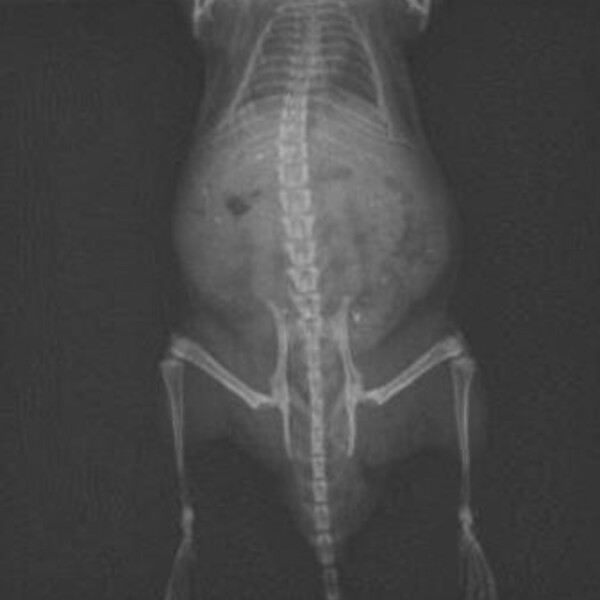

X-ray

The Min X-ray SA100 portable unit offers high resolution x-ray imaging with AGFA CR30 Xe digital MUSICA™ processing and image analysis with NX software. Zoom in and adjust image contrast, frequency and density for optimal feature identification and viewing on the 2MP monitor. Images in DICOM or jpeg format burned to disk for your files. Track the progress of your orthopedic project from immediate post-operative imaging through critical periods of change.